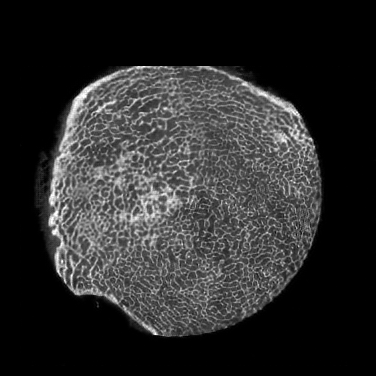

III-F1 Practical SRCT Implementation Details

We first obtained LRCT and HRCT images using a deceased mouse on the same scanner with two scanning protocols. The micro-CT parameters are as follows: X-ray source circular scanning, 606060 kVp, 134134134 mAs, 720720720 projections over a range of 360360360 degrees, exposure 505050 ms per projection, and the micro-CT images were reconstructed using a conventional filtered back projection algorithm (FDK): HRCT image size 1450×1450145014501450\times 1450, 600600600 slices at 48μm48𝜇𝑚48~{}\mu m isotropic voxel size, and the LRCT image size 725×725725725725\times 725, 300300300 slices at 24μm24𝜇𝑚24~{}\mu m isotropic voxel size. Then, we compared with the state-of-the-art super-resolution methods. Since the real data are unmatched, we accordingly evaluated our proposed GAN-CIRCLEs and GAN-CIRCLEu networks for 111X resolution improvement.

The quantitative results were summarized for all the involved methods in Table II. The PSNR-oriented approaches, such as FSRCNN, ESPCN, LapSRN, and our G-Fwd, yield higher PSNR and SSIM values than the GAN-based methods. It is not surprising that the PSNR-oriented methods obtained favorable PSNR values since their goal is to minimize per-pixel distance to the ground truth. However, our GAN-CIRCLEs and GAN-CIRCLEu achieved the highest IFC among all the SR methods. Our method GAN-CIRCLEs obtained the second best results in term of SSIM. The visual comparisons are given in Figs. 7 and 8. To demonstrate the robustness of our methods, we examined anatomical features in the lung regions and the bone structures of the mice, as shown in Figs. 7 and 8 respectively. It is observed that the GAN-based approaches performed favorably over the PSNR-oriented methods in term of perceptual quality as illustrated in Figs. 7 and 8. Fig. 7 confirms that the PSNR-oriented methods produced blurry results especially in the lung regions, while the GAN-based methods restored anatomical contents satisfactorily. In Fig. 8, it is notable that our methods GAN-CIRCLEs and GAN-CIRCLEu performed better than the other methods in terms of recovering structural information and preserving edges. These SR results demonstrate that our proposed methods can provide better visualization of bone and lung microarchitecture with sharp edge and rich texture.